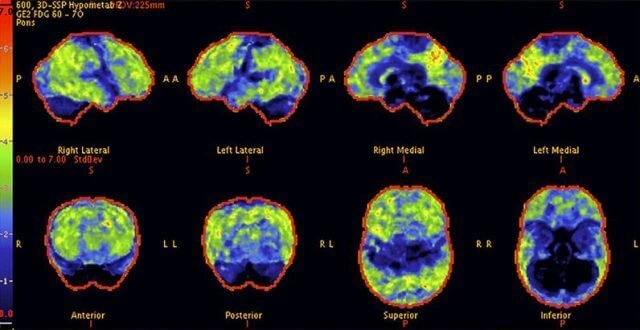

Above: A 68-year-old woman with a 10-year history of cognitive issues. Previous PET scans showed significant metabolic decline, indicating Alzheimer's.